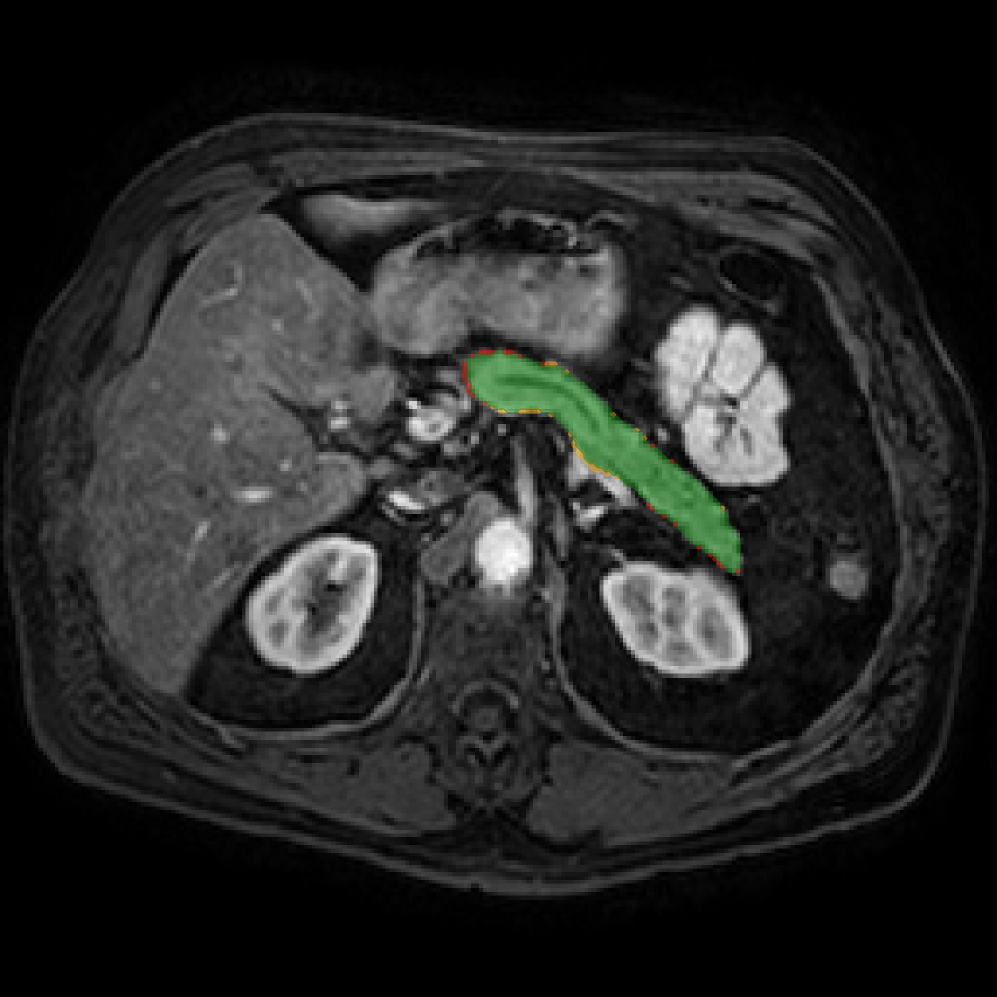

Accurate pancreas segmentation is a critical prerequisite for precise cyst analysis and classification. Recently, we developed PanSegNet [zhang2025large], a novel segmentation architecture incorporating linear self-attention layers [zhang2022dynamic] within the nnUNet framework [isensee2021nnu] to enhance global information modeling capabilities while maintaining computational efficiency (Fig. 1). PanSegNet demonstrated exceptional segmentation performance across both T1W and T2W modalities, achieving mean dice scores of 86.817.30% and 89.626.38%, respectively (Table 1, Fig. 2b-c). This performance significantly exceeded that of Swin-UNETR [hatamizadeh2021swin], one of the most used state-of-the-art transformer-based medical segmentation models, which achieved dice scores of 79.091.40% and 76.290.66% for T1W and T2W, respectively (). In this study, we integrated PanSegNet into our Cyst-X engine along with a classifier for risk prediction. In Section 2.2, we show that the choice of segmentation model affects the classification results. The performance advantage of PanSegNet was consistent across all seven medical centers, demonstrating robust generalization despite variations in imaging protocols and equipment (Table 1). This cross-institutional reliability is particularly important for clinical applications, where model performance must remain consistent regardless of imaging site or acquisition parameters.

Each patient was categorized into one of these three ground truth classes: no risk/control, IPMN low-risk, or IPMN high-risk. To evaluate variability in image acquisition, we applied uniform manifold approximation and projection (UMAP) to image quality indicators, revealing distinct clustering patterns by imaging center and slice thickness. This heterogeneity reflects real-world clinical variability, enhancing the dataset’s generalizability while presenting technical challenges for model development. Fig. 6 shows examples of low-grade, high-grade, and cancer developing IPMNs from the Cyst-X dataset.